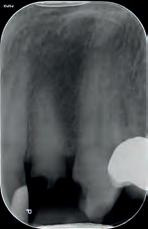

Bij deze patiënte was gebitselement 36 erg pijnlijk en had een extreem pijnlijk reactie op een koudetest. Patiënte was al even niet meer bij de tandarts geweest en had al twee dagen niet kunnen slapen van de kiespijn. Op de röntgenfoto (afbeelding 1) is onder andere te zien dat gebitselement 36 een diepe restauratie heeft, de restauratie van gebitselement 37 secundaire cariës toont en dat er distaal van de 37 een forse brok subgingivaal tandsteen aanwezig is. Er is geen duidelijk periapicaal granuloom

te zien en dat maakt dat de diagnose een irreversibele pulpitis is. Het plan was om een pulpotomie te doen.

Afbeelding 1. Gebitselement 36 heeft een diepe restauratie en er is, secundaire cariës mesiaal van de 37 (en een forse brok subgingivaal tandsteen). Er is geen duidelijk periapicaal granuloom te zien. Let op de morfologie van de mesiale radix, hier lijkt in retrospect een aanwijzing voor een mid-mesiaal kanaal.